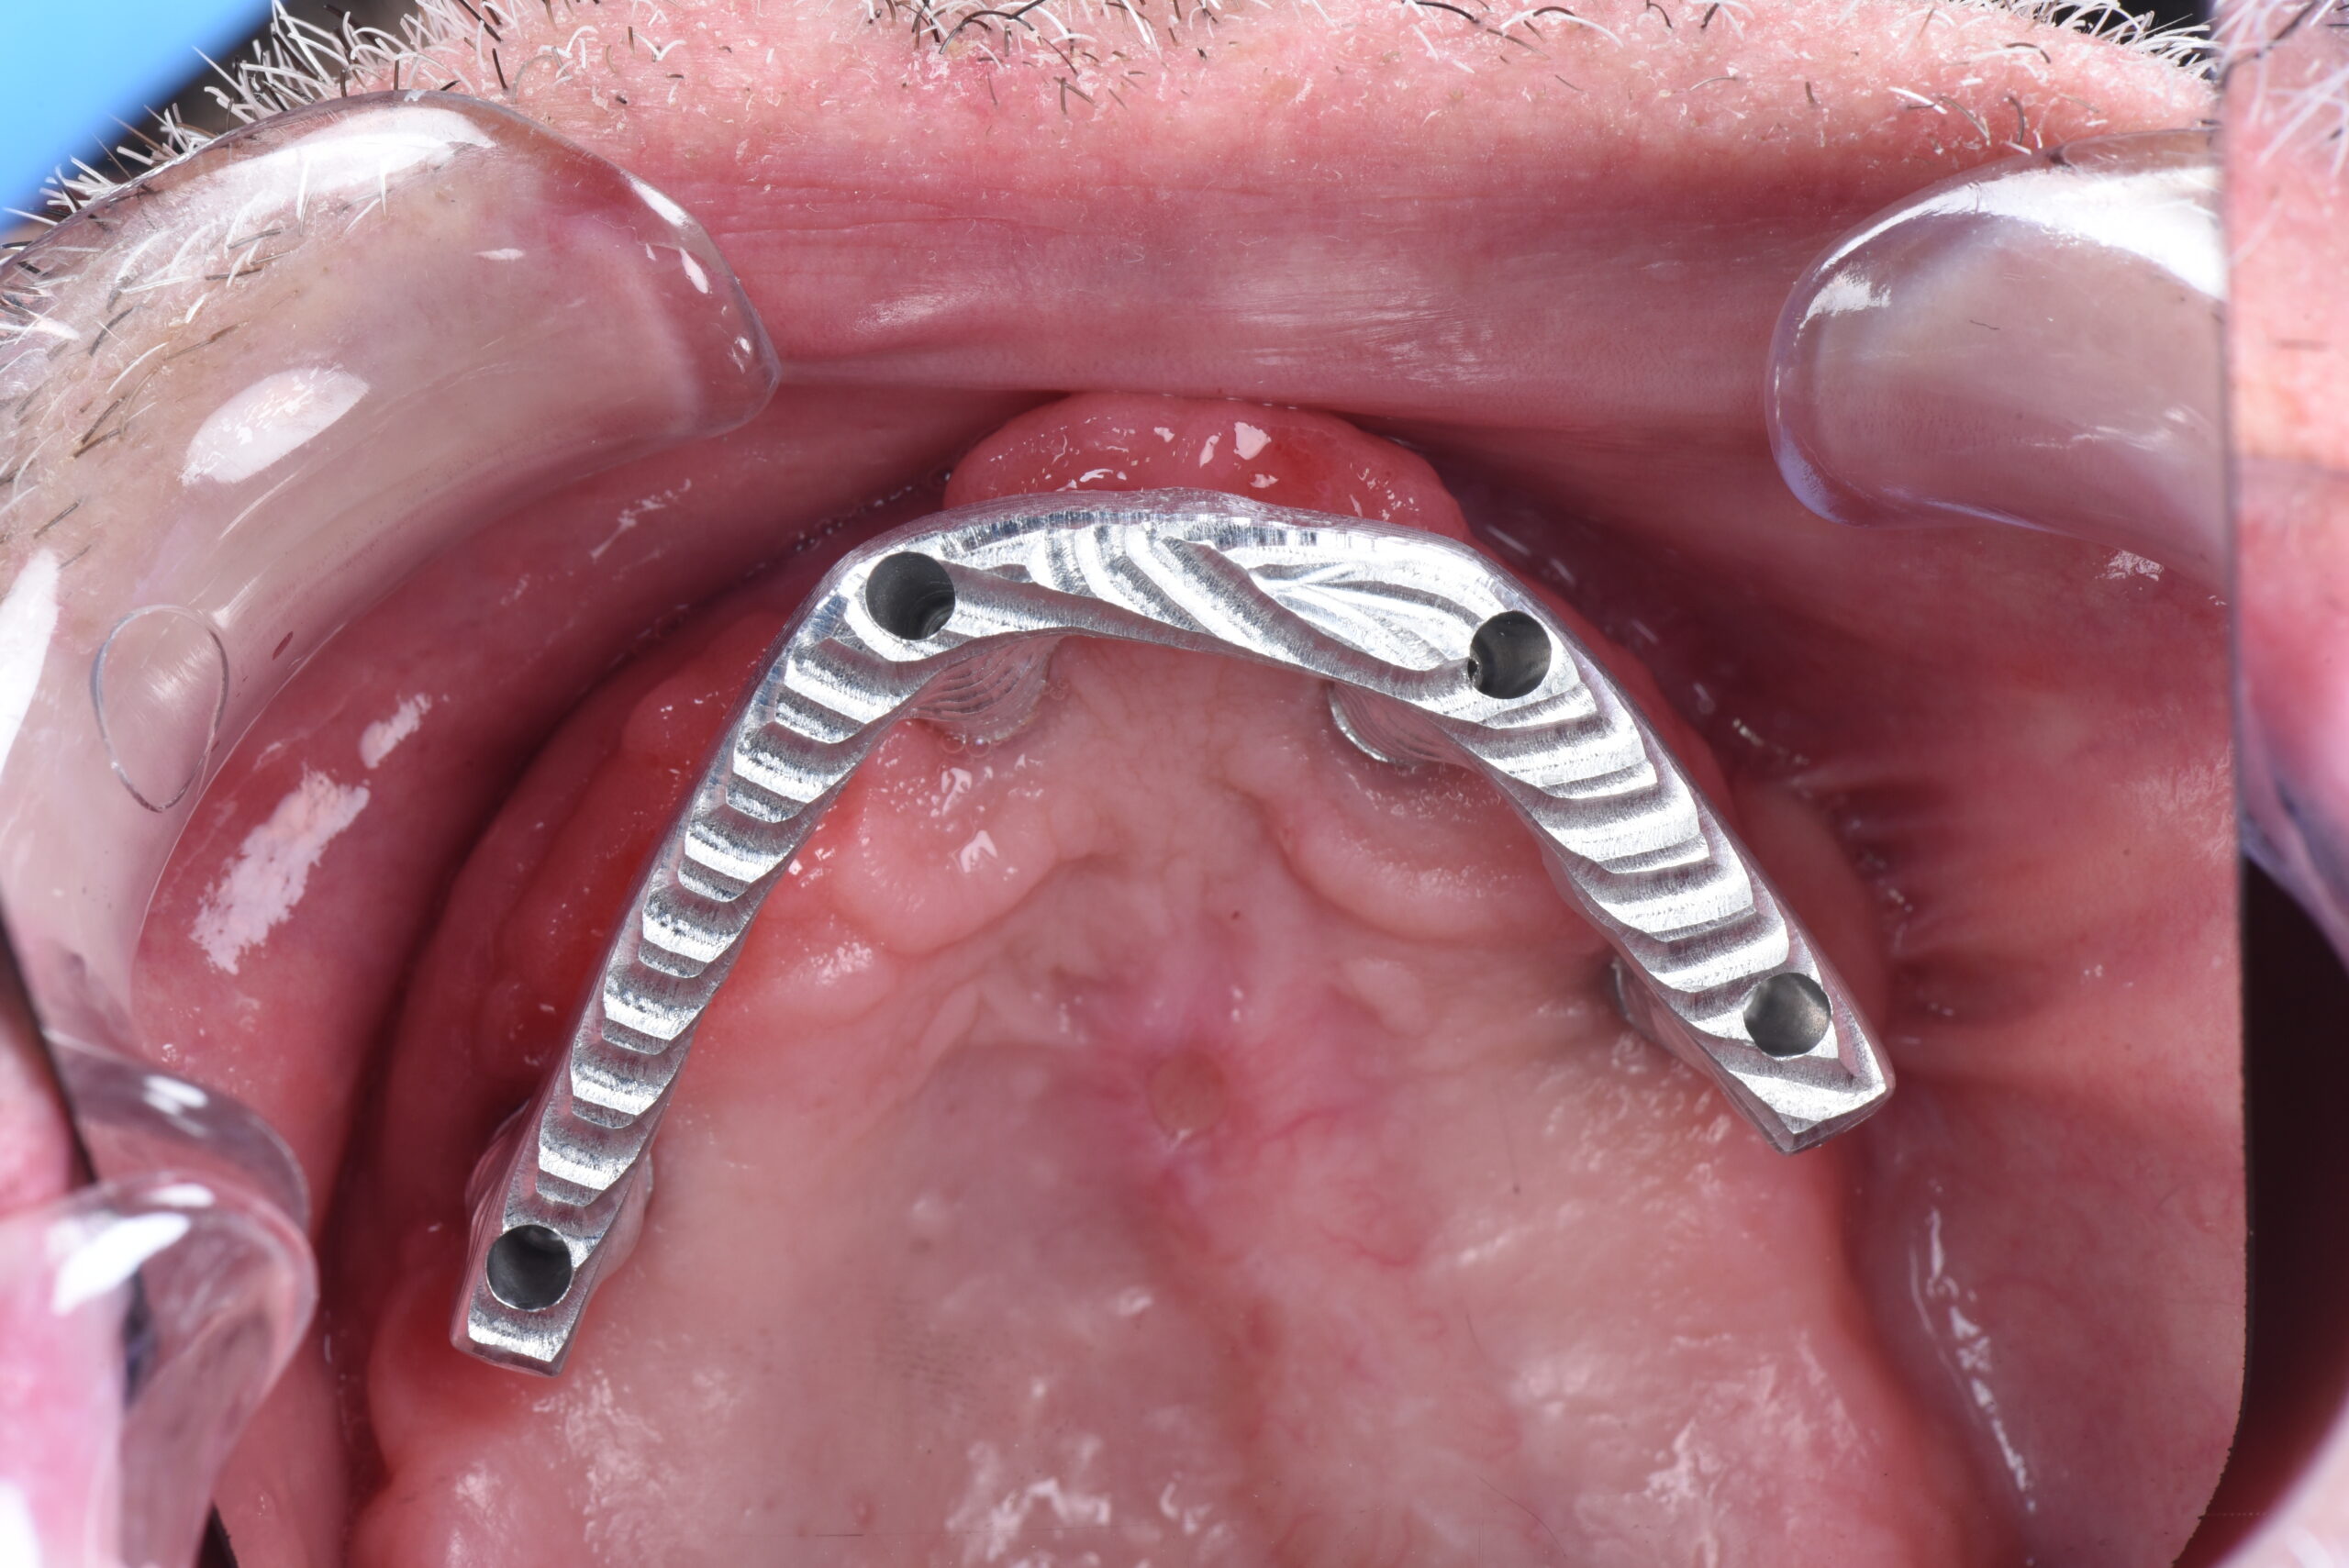

María Paz llevaba muchos años con una prótesis completa superior y pocas piezas en la parte inferior. El paso del tiempo provocó una gran pérdida ósea, lo que dificultaba la colocación de implantes convencionales. Durante años sufrió una masticación deficiente y las incomodidades de una prótesis removible. Con un tratamiento avanzado, volvió a disfrutar de la comodidad y la seguridad al sonreír.

Colocación de implantes cigomáticos

Implantes en el maxilar inferior con injerto de encía

Prótesis de cerámica y titanio

Una Boca nueva recuperando la oclusion de la paciente y estabilizando su mordida en clase 1. Evitando la patologia articular y devolviendo la funcion y la sonrisa a la paciente